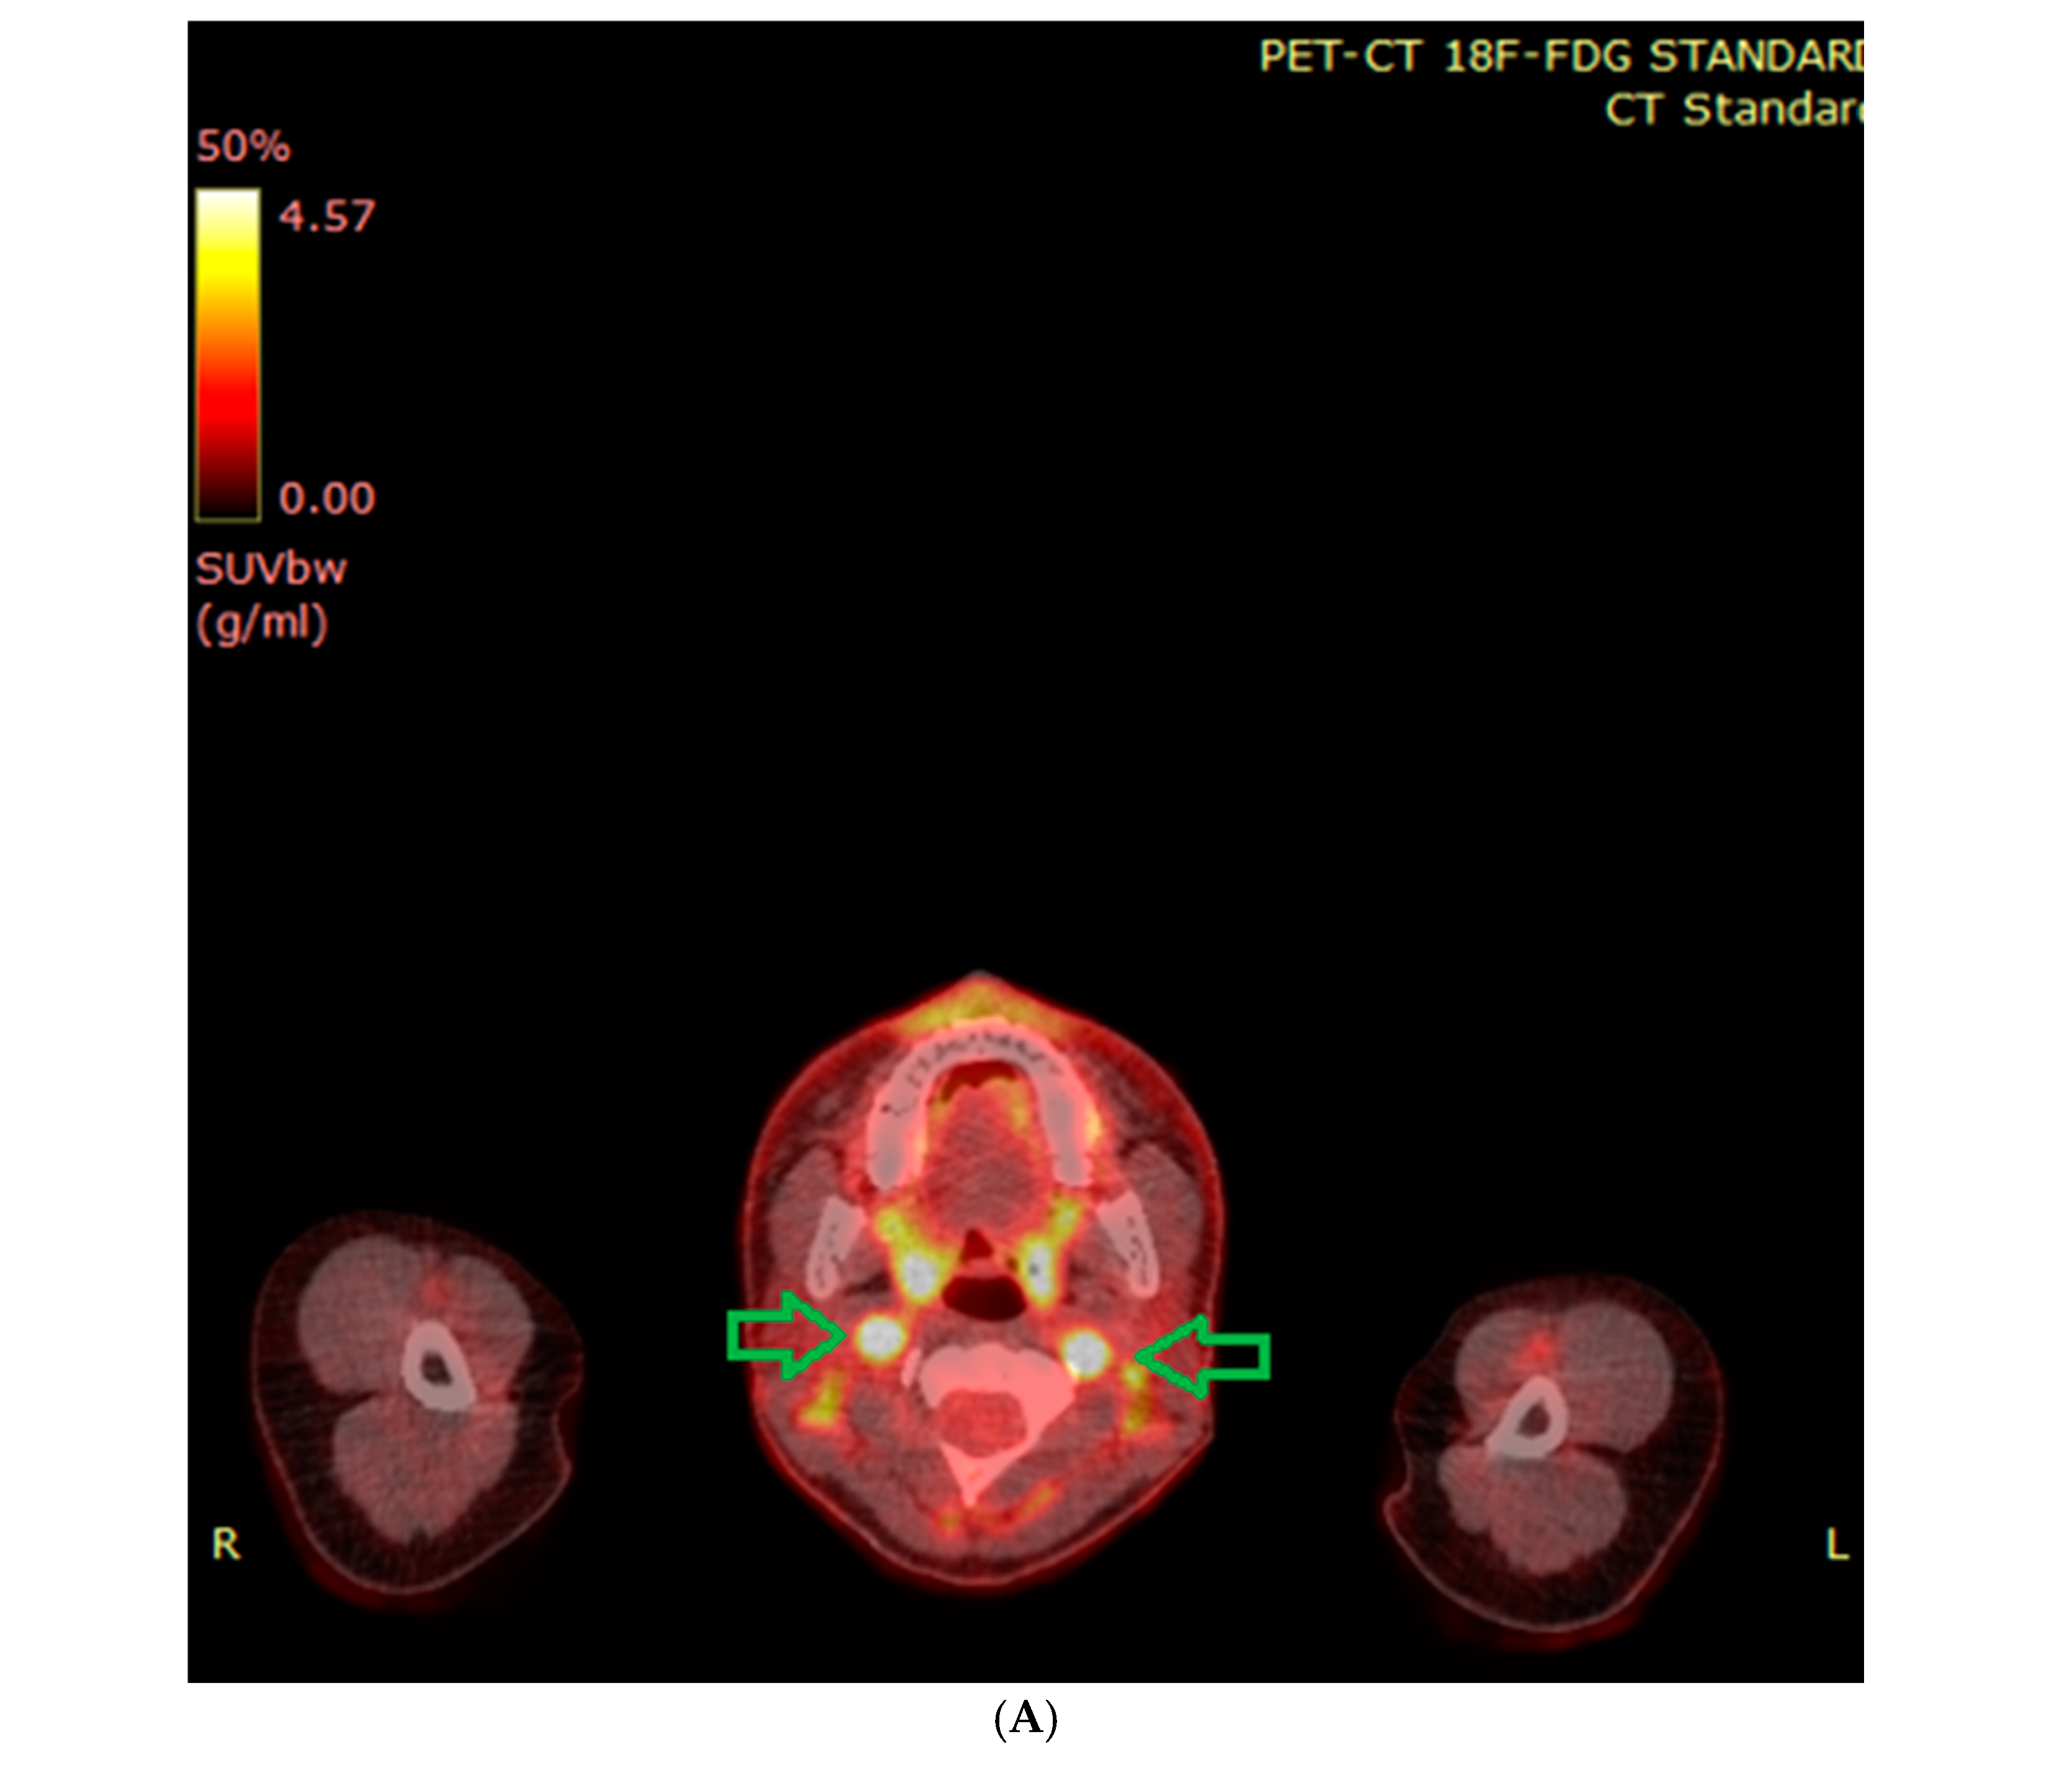

6.2. Functional Imaging

7.9. External Beam Radiotherapy (ERBT) and Hypofractionated Stereotactic Radiotherapy (hSRT)